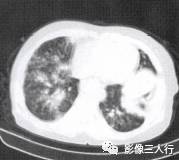

胸部CT图像显示,在含气少的致密肺的背景上见到含气的支气管,表现为两种形态: ①在大片肺实变病灶内的细条状空气密度影;②直径Imm的小泡状空气密度影,连续的几 个层面都能出现(图2、图3)。该征象表明:①近侧气道通畅;②肺泡内的空气经吸收(肺不张)或取代(肺炎、肺癌),或两者综合而消失。通畅含气的支气管在肺泡实变高 密度区内表现为管腔内低密度充气轮廓。